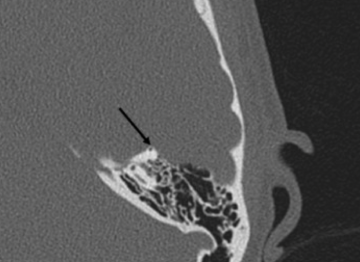

Diagnosis of SSCD is confirmed using a combination of physical examination, physiological testing such as Cervical and Ocular Vestibular Evoked Myogenic Potential (VEMP) testing; in conjunction with temporal bone high resolution computed tomography (CT) imaging to visualize the defect.

High-resolution computed tomography (CT) scans of the temporal bone is crucial for physicians to diagnose, confirm, and locate SSCD. Sometimes CT scans can overestimate the SSCD when the size is below 3 mm. Thus, it is important to conduct other clinical and neurophysiological tests to compliment the radiological findings.